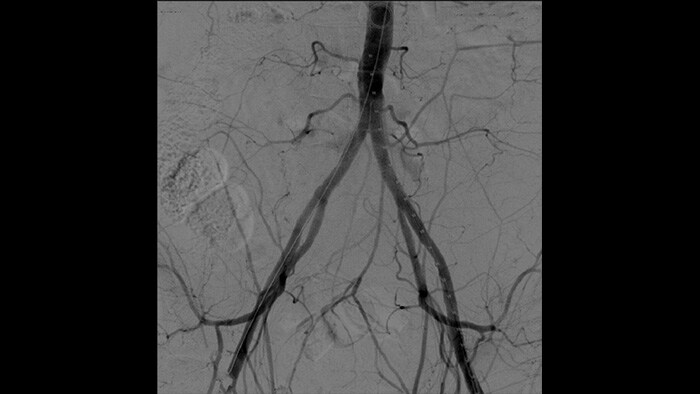

With the Philips Zenition mobile C-arm, Dr. Vila is obtaining outstanding high-quality images that allow him to perform most vascular procedures at the low dose setting.

With the Zenition, our DSA image quality has improved greatly. We no longer see a grainy image. We just see a very clear image."

Dr. R. Vila, MD

Digital subtraction angiography (DSA) is used in interventional vascular procedures to clearly visualise blood vessels by removing structures that can obscure vessel visibility. Roadmap fluoroscopy overlays a previously acquired subtracted contrast image on the live fluoroscopy, allowing you to track a device without reinjecting contrast.